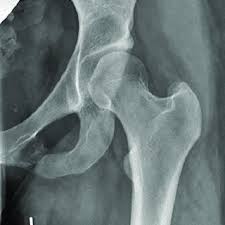

Van neck odelberg disease. Van Neck disease VND is a benign skeletal abnormality of children involving a hyperostosis of the ischiopubic synchondrosis IPS seen on radiographs. BACKGROUND Van Neck disease VND is a benign skeletal abnormality of children involving a hyperostosis of the ischiopubic synchondrosis IPS seen on radiographs. Odelberg disease - Synonym s.

The different characteristics by images from simple radiography computed tomography MRI and bone. Van Neck-Odelberg disease is a benign process that develops in children between the ages of 4 and 16 years. Van Neck-Odelberg disease or ischiopubic osteochondritis is a rare cause of pain in the pediatric pelvis due to late closure in synchondrosis ischiopubic whose main symptom is an asymmetric pain that can cause a limitation in movement or limp.

Its radiological features may mimic stress fracture neoplasm osteomyelitis or posttraumatic osteolysis. Differential diagnosis such as stress fractures osteomyelitis tuberculosis post-traumatic osteolysis or any neoplasia is need be ruled out to arrive at diagnosis. Medical Eponyms Farlex 2012.